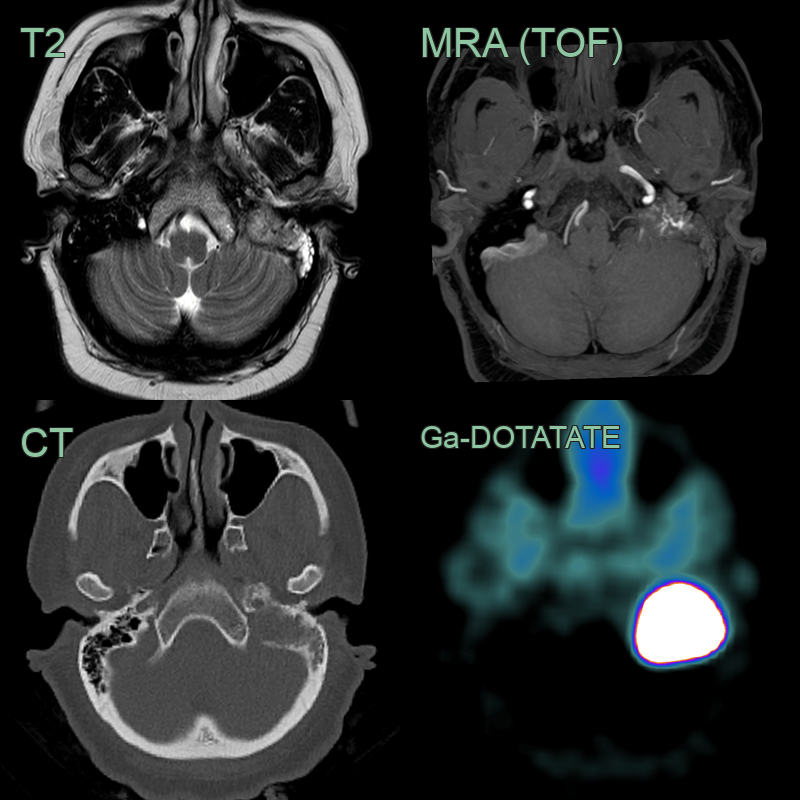

- 40-year-old patient presented with hearing loss and facial palsy.

- MRI showed a lesion in the left jugular foramen and petromastoid bone with evidence of vascularity on T2-weighted imaging (i.e., flow voids) and time-of-flight angiography. Ga-DOTATATE PET showed avid tracer uptake as expected in a paraganglioma.